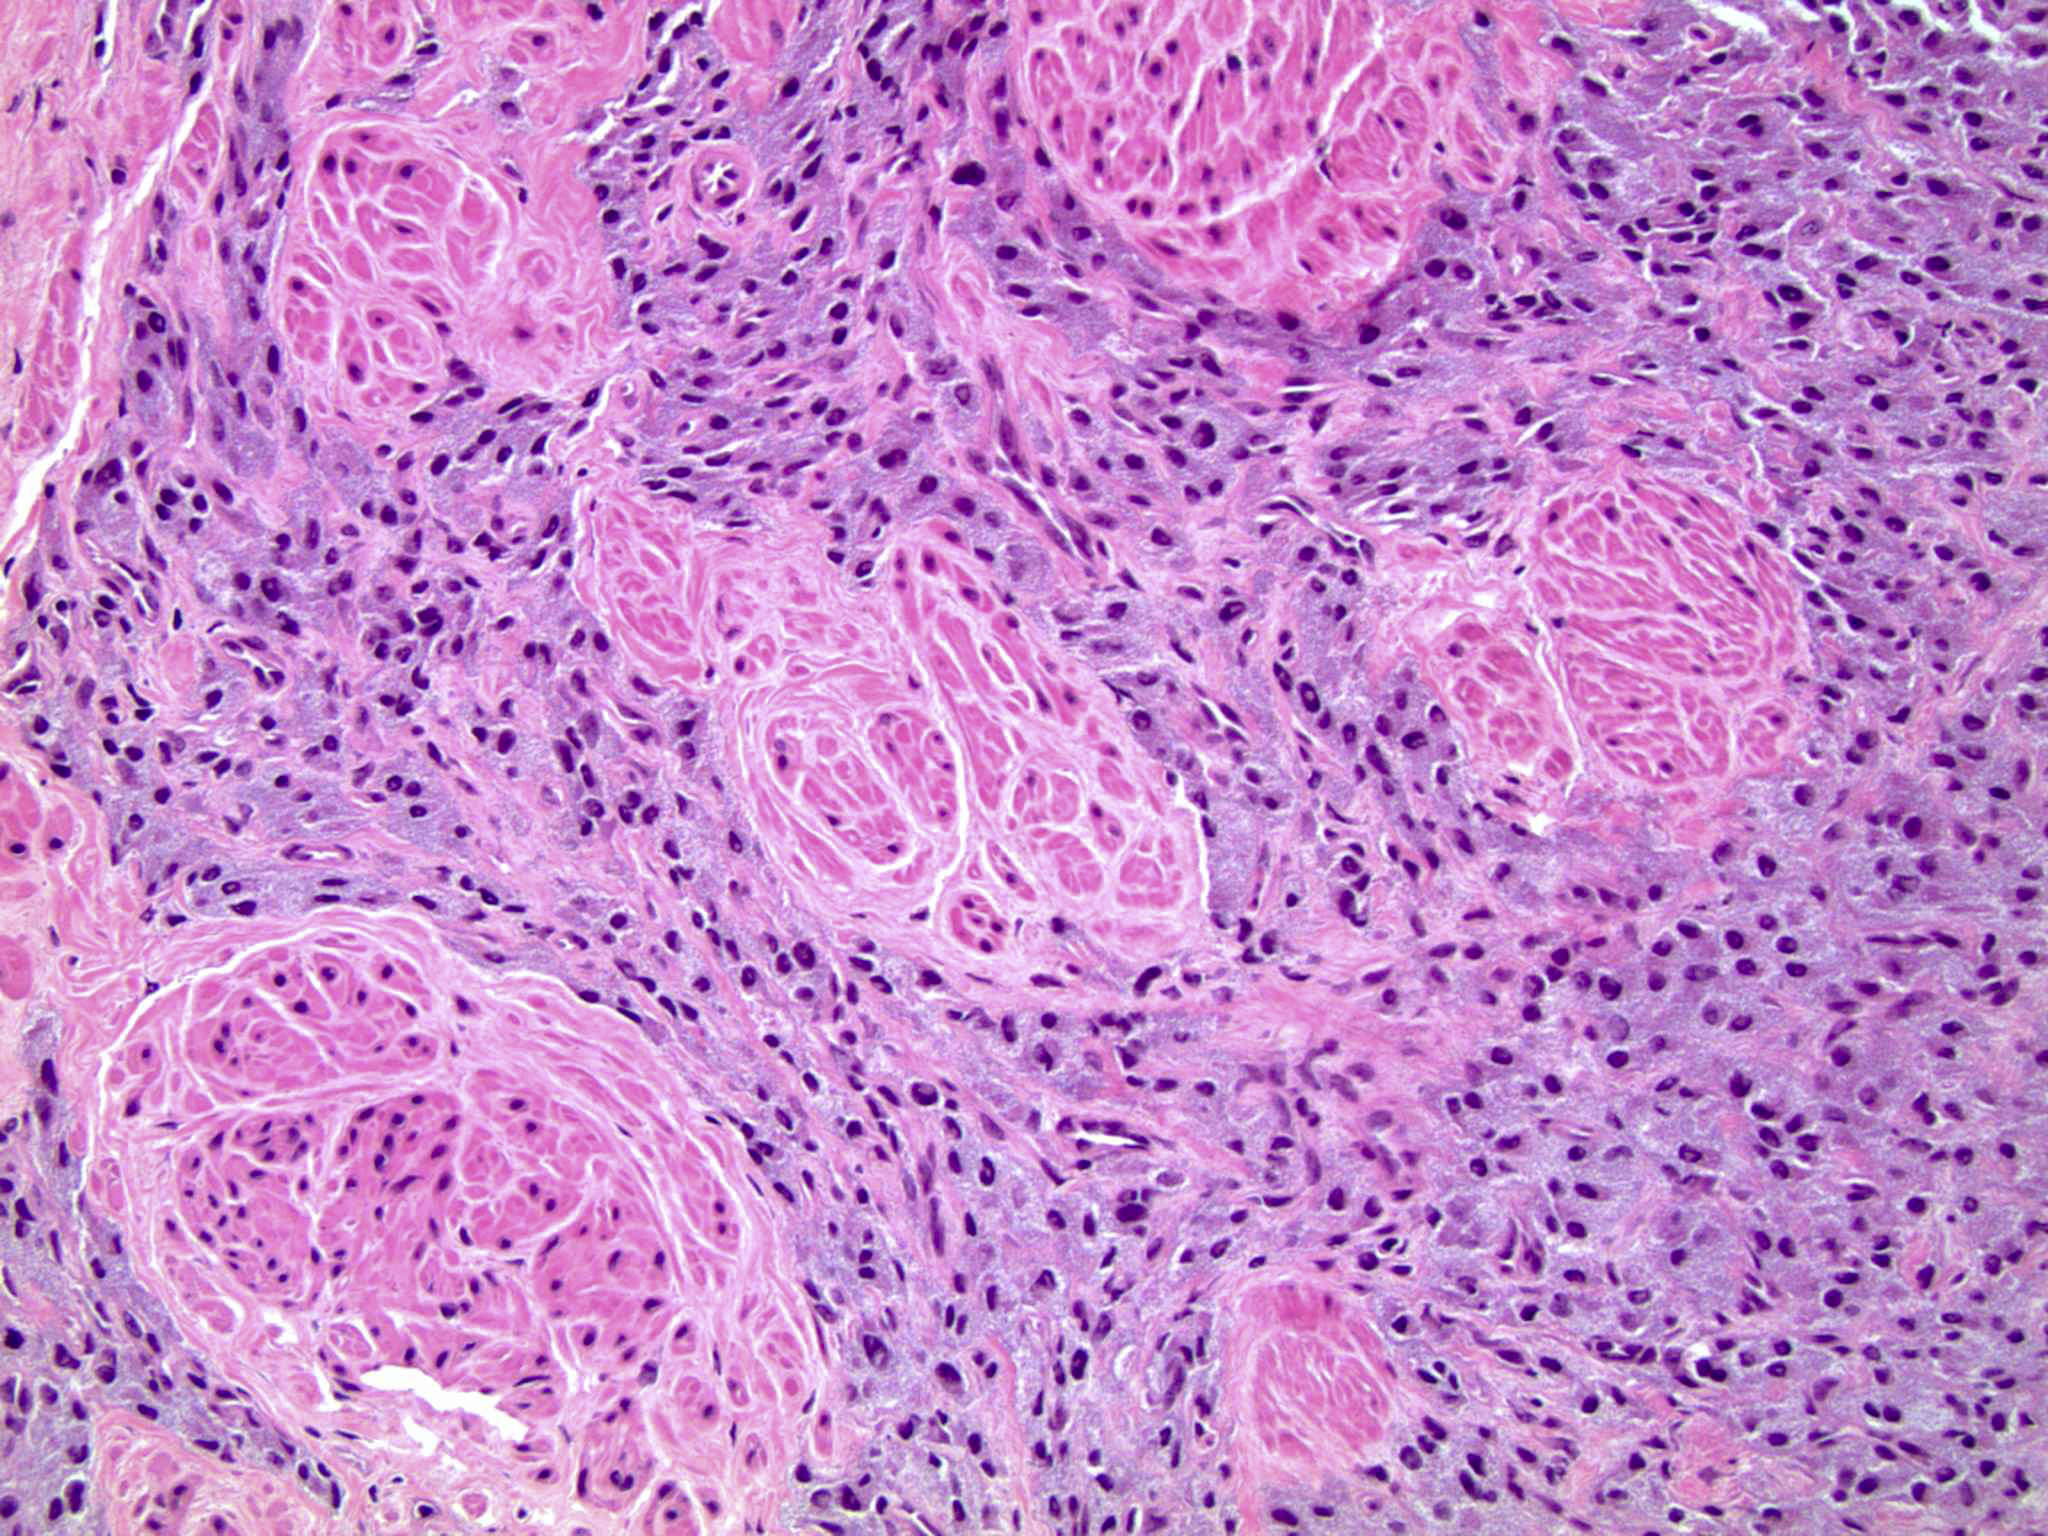

- Classic histologic morphology: monomorphic cells with abundant eosinophilic / amphophilic cytoplasm arranged in a nested / zellballen pattern and separated by fibrovascular septa with sustentacular cells

Microscopic (histologic) description

- Typical morphology: epithelioid cells with abundant, eosinophilic / amphophilic, granular cytoplasm and round / ovoid, vesicular / salt and pepper nuclei, arranged in a nested / zellballen pattern and separated by fibrovascular septae with sustentacular cells (Am J Surg Pathol 2004;28:94, World J Clin Cases 2014;2:591, Endocr Pathol 2022;33:90)

- May have focal pleomorphism, nuclear hyperchromasia, low mitotic activity or clear cytoplasm

Microscopic (histologic) images

Contributed by Theodorus H. van der Kwast, M.D., Ph.D., Michelle R. Downes, M.D., Debra L. Zynger, M.D. and David Cohen, M.B.B.Ch., M.D.

- Microscopic description: This specimen shows an unencapsulated, monomorphous population of round tumor cells in a nested / zellballen pattern with delicate vascular septa and intervening extravasated red blood cells. It predominantly involves the lamina propria of the bladder but in 1 tissue piece clearly involves muscularis propria. The tumor cells have abundant amphophilic cytoplasm and vesicular chromatin with occasional small nucleoli. There is no necrosis, diffuse growth pattern or vascular space invasion identified. The mitotic count is (maximally) 1/10 high power fields. Immunohistochemistry shows the tumor cells to be positive for GATA3 with strong and diffuse expression of synaptophysin and chromogranin, as well as retention of SDHB staining. The tumor cells are negative for AE1 / AE3, HMWK and p63. The Ki67 proliferation index is < 1%. S100 shows faint nuclear and cytoplasmic staining with occasional sustentacular cells identified.

- Microscopic description: Sections show unremarkable surface urothelium with a lesion in the deep lamina propria comprised of large eosinophilic cells with hyperchromatic, focally enlarged nuclei with occasional intranuclear inclusions. A fine vascular plexus is identified in some areas. Necrosis and hemorrhage are not identified. Mitotic rate = 1/10 high power fields (field of view [FOV] = 0.55 mm). The lesion extends to the cauterized base of the specimen. Immunostains confirm the lesion expresses synaptophysin, chromogranin and GATA3. SDHB is retained. AE1 / AE3, CD45, p63 and NKX3.1 are negative.